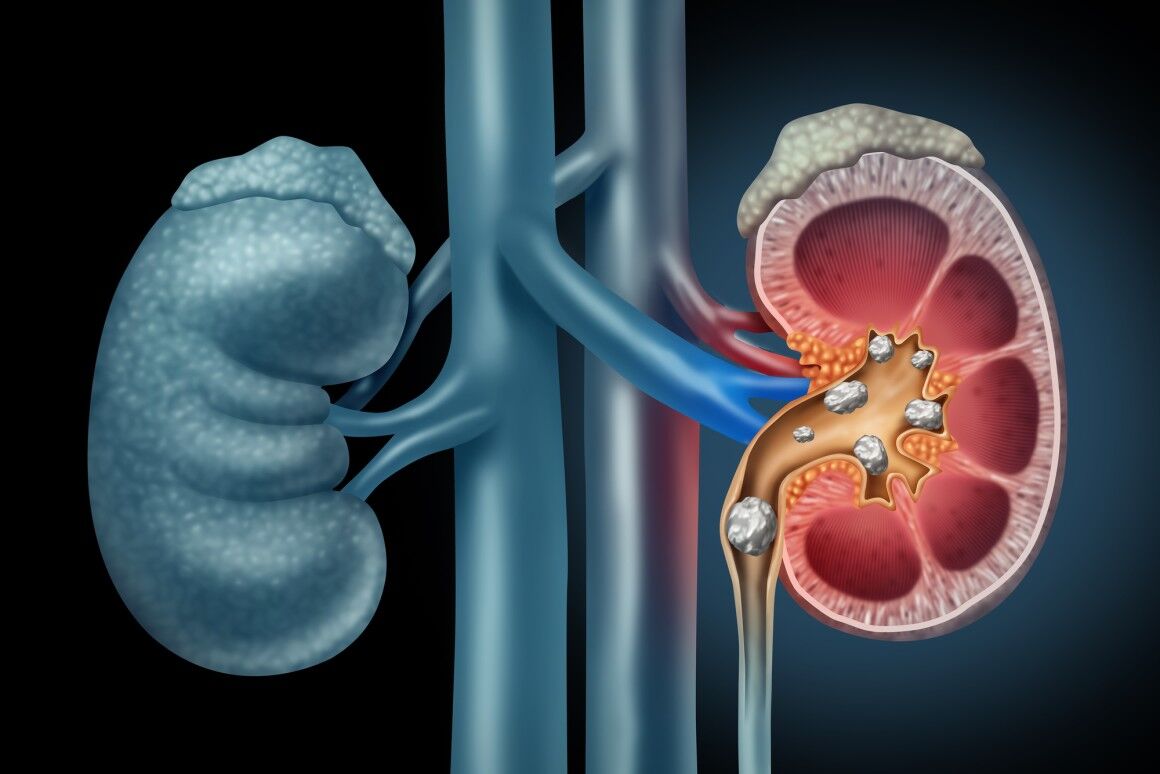

در هر ساعت کلیه های بدن انسان حدود ۷ لیتر مایع را از خون جدا می کنند این مایع را تصفیه کرده و مواد مفید و سودمند آن را به خون بازمی گردانند و مواد مضر آن را از راه میزنای به مثانه می فرستد تا دفع شوند. کجای بدنتان درد می کند مراجعه کنید آیا کلیه تان درد می کند درد کلیه در اثر عفونت کلیه یا آسیب رسیدن به آن ایجاد می شود. اما کار و وظیفه کلیه ها در بدن چیست بیا یاد بگیریم. زمانیکه کلیه ها بدرستی فعالیت کنند مواد زائد از بدن داخل ادرار ترشح می شوند همچنین کلیه ها در تنظیم سایر مواد معدنی در بدن مانند.

کلسیم و فسفر که برای تشکلی استخوان لازمند کمک می کنند مواد. کلیه ها با تولید ادارد در دفع مواد زاید تعادل الکترولیتی تنظیم هورمونی تنظیم فشار خون و هوموستازگلوکز نقش دارند. آناتومی کلیه انسان در بدن انسان به این شکل است که کلیه ها دو عضو لوبیایی شکل در دستگاه ادراری بوده و به دفع مواد زائد به صورت ادرار کمک می کنند. یکی از مهم ترین وظایفی که کلیه ها در بدن بر عهده دارند پاک کردن و تصفیه خون از زباله هاست.